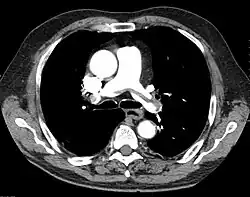

"Saddle" embolism on CT. The filling defect in the pulmonary artery is the clot.

A pulmonary embolism (PE) is an obstruction of the pulmonary arteries.[13] Deaths from PE have been estimated at ~100,000 per year in the United States. However, this may be higher in recent years.[16] Most often, the obstruction is a blood clot that traveled from elsewhere in the body. Most commonly, this is from a deep vein thrombosis (DVT) in the legs or pelvis.[13] Risk factors are conditions that increase the risk of clotting. This includes genetic (factor V Leiden) and acquired conditions (cancer).[17] Trauma, surgery, and prolonged bed-rest are common risks. COVID-19 is a recent risk factor.[18]

A chest X-ray can rapidly identify a pneumothorax, seen as absence of lung markings. Ultrasound can show the lack of lung sliding. However, imaging should not delay treatment.[8] CT angiography is the standard of diagnosis of pulmonary embolism. Clots appear in the vasculature as filling defects.[18]